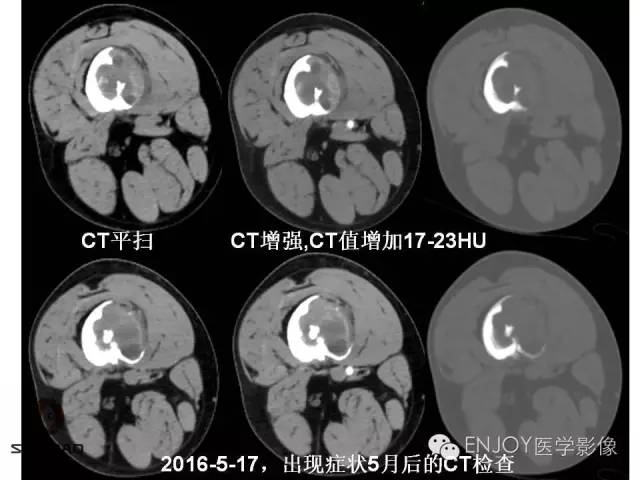

1、病灶的定性诊断是?(单选)

A:良性肿瘤

B:恶性肿瘤

C:非肿瘤

2、你的诊断(单选)

骨肉瘤(传统型)

骨肉瘤(毛细血管扩张型)

多形性肉瘤(以往称为:恶性纤维组织细胞瘤)

软骨肉瘤(2-3级)

转移瘤